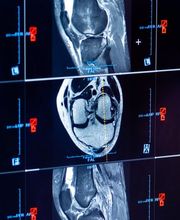

Modernste Technik, rasche Termine, ein umfassendes Versorgungskonzept mit individueller Diagnostik auf neuestem Stand und meine langjährige Erfahrung sind die Grundlagen der MRT Radiologie Privatpraxis in Stuttgart. In zentraler Lage biete ich Ihnen mit meiner hochwertig ausgestatteten Praxis modernste Diagnostik mit einem MRT der neusten Bauart mit hochauflösenden und aussagekräftigen Bildern, für eine fundierte und sichere Diagnostik. Ich bin spezialisiert auf die MRT Vorsorge: Ob Ganzkörper MRT, MRT des Kopfes, Schlaganfall-Prophylaxe, MRT des Rückens oder der Gelenke. Selbstverständlich bin ich auch bei allen akuten und chronischen Beschwerden für Sie da. Wann immer der Blick in Ihr Innerstes gefragt ist, bin ich an Ihrer Seite.